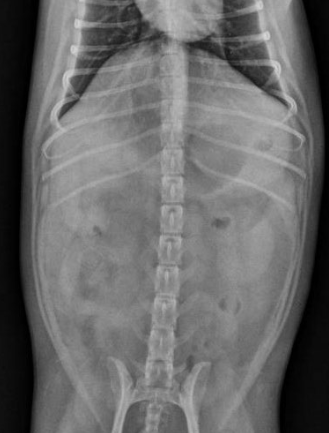

what is going on here?

enlarged kidney, renal carcinoma

there is one tiny kidney and one huge kidney: compensatory hypertrophy